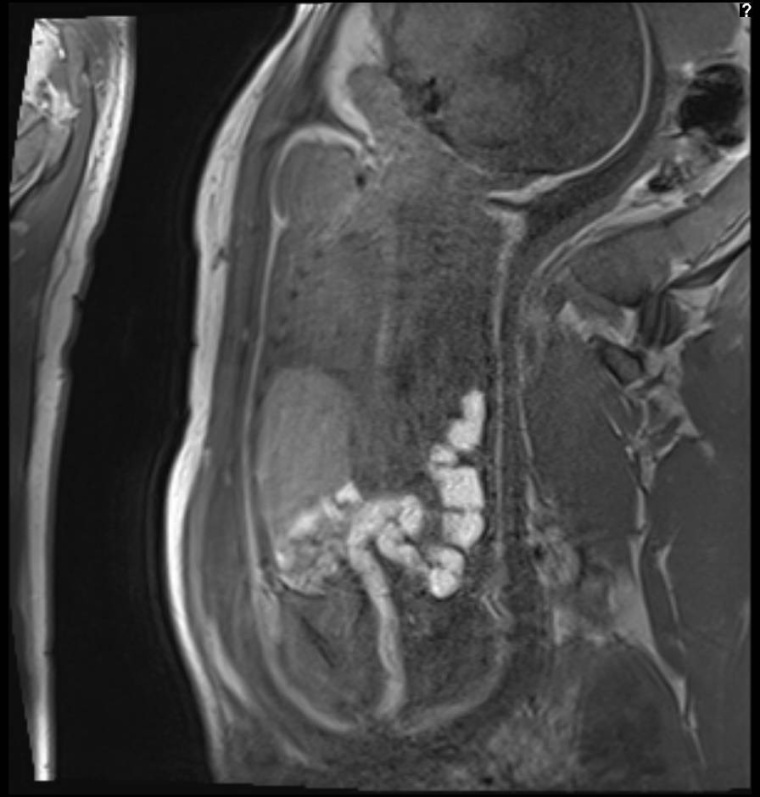

Im Bereich der Hirndiagnostik und bei Tumorerkrankungen ist die MRT-Diagnostik allerdings konkurrenzlos und daher zwingend und hat sich in den vergangenen Jahren zur zweithäufigsten Schnittbild-Untersuchungsmodalität in der Kinderradiologie entwickelt. CT-Untersuchungen nehmen dagegen aus strahlenhygienischen Gründen nur noch einen marginalen und zudem kontinuierlich abnehmen Anteil an der Schnittbilddiagnostik im Kindesalter ein. Indikationsgerechte CT-Diagnostik kommt nur noch beim kindlichen Trauma sowie in eingeschränktem Maße auch bei der Lungendiagnostik zum Einsatz.

Wir haben mit einem in der Kinderradiologie aufgestellten 3.0T-MRT über einen Zeitraum von über fünf Jahren auch im Abdomen- und Thoraxbereich beste Erfahrungen sammeln können. Dessen höhere Feldstärke wirkt sich positiv auf Untersuchungszeiten und Bildqualität bei Kindern aus, während die bei volumenkräftigen erwachsenen Patienten bekannten Artefakte aufgrund der kleineren Körperdurchmesser bei 3.0 T nicht so relevant werden.